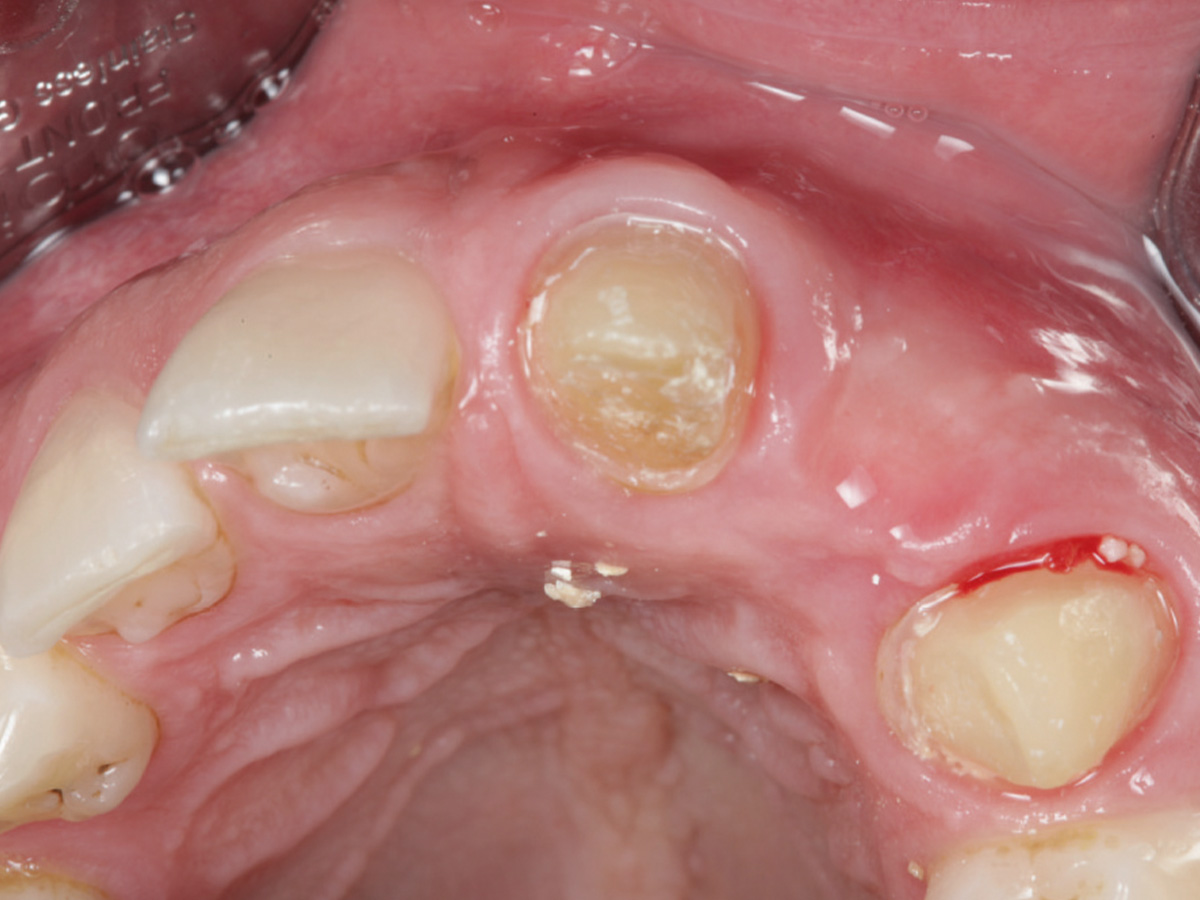

Abbildung 12

Regenerierter Alveolarkamm vor der prothetischen Versorgung.